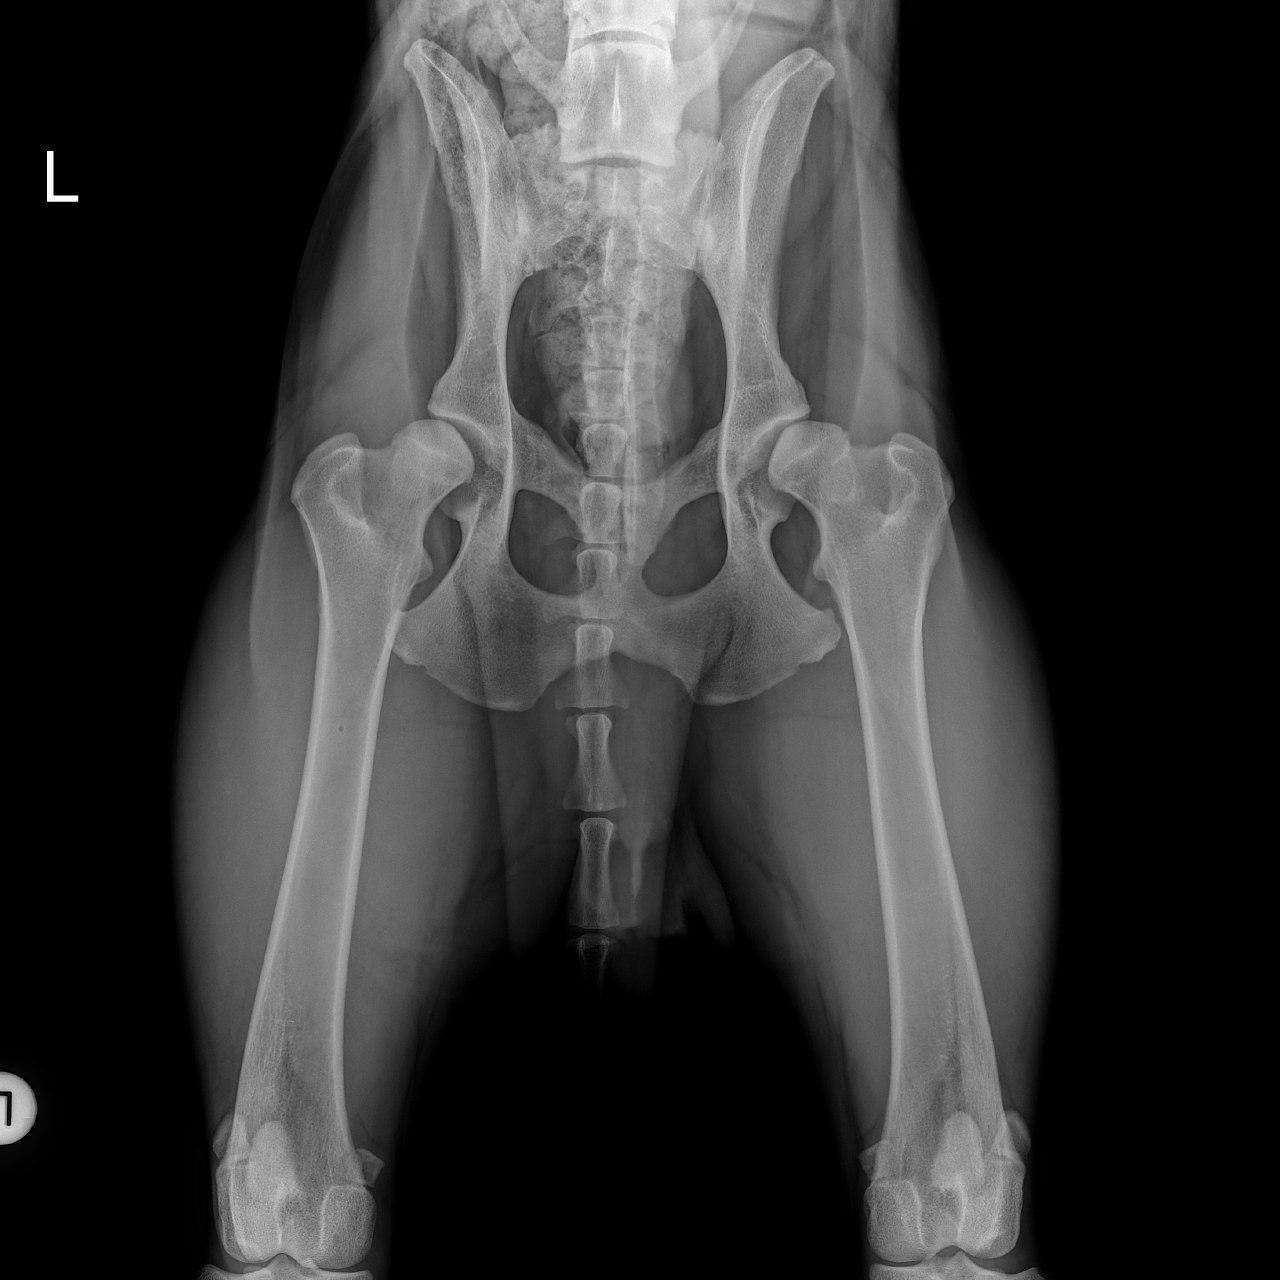

Ich stelle hier auch mal ein Bild ein.

Benny Puuh kann es sein, dass das bei Simba sogar noch schlimmer aussieht, als bei deinem Knuffel?

• Immer links, habe ich den Eindruck. Bei Sam ist das auch so. Die linke Hüfte hat mehr von der HD abbekommen, als rechts. Das ist scheinbar bei euren auch so. Komisch, dass das so ist.